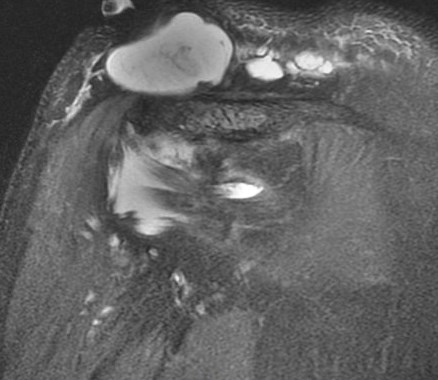

Figure 2 for case Geyser phenomenon

Figure 2